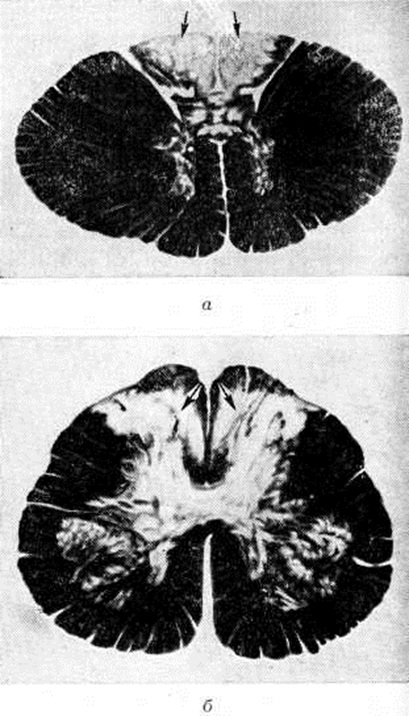

Патологическая анатомия. Макроскопически спинной мозг (смотри полный свод знаний) уплощен и истончен, его задние канатики и задние корешки спинномозговых нервов истончены и сморщены. Микроскопически в начальной стадии Спинная сухотка выявляют лептоменингит (смотри полный свод знаний: Менингит) вокруг интрадуральной части задних корешков и в области задних канатиков с инфильтрацией лимфоцитами и плазматическими клетками, а также пролиферативные изменения в стенках сосудов, соединительной ткани, в пери и эндоневрии задних корешков. Описанные выше изменения более отчетливы в нижних отделах спинного мозга — крестцовом и поясничном. В стадии выраженной Спинная сухотка поражение характеризуется дегенерацией центральных отростков клеток спинномозговых узлов, при этом сами узлы обычно мало изменены. Особенно значительные дегенеративные изменения отмечают в экстрадуральной части задних корешков и в зоне их вступления в спинной мозг, где они сдавливаются фиброзно-утолщенными оболочками и разросшейся краевой глией (смотри полный свод знаний: Нейроглия). Дегенеративные изменения (распад миелиновой оболочки и осевых цилиндров аксонов, образующих задние канатики) волокон корешков распространяются вверх по задним канатикам спинного мозга. В заключительной стадии процесса на месте атрофированных волокон задних корешков и канатиков разрастается фибриллярная глия pi соединительная ткань. В поясничном и крестцовом отделах спинного мозга распад миелина начинается в медиальной части задних канатиков. В грудных и шейных сегментах спинного мозга дегенерации подвергается вся область задних канатиков (рисунок 1). Её обнаруживают и в периферических отростках клеток спинномозговых узлов, входящих в состав образований периферической нервной системы (сплетений, нервов), а также в различных отделах высшая нервная система Во многих случаях выявляют дегенерацию волокон черепно-мозговых (черепных) нервов в их внутричерепном отрезке. На разных стадиях Спинная сухотка могут обнаруживаться инфильтративные, пролиферативные и рубцовые изменения в оболочках головного мозга, а также поражение сосудов мозговых оболочек.

Рис. 1. | ||